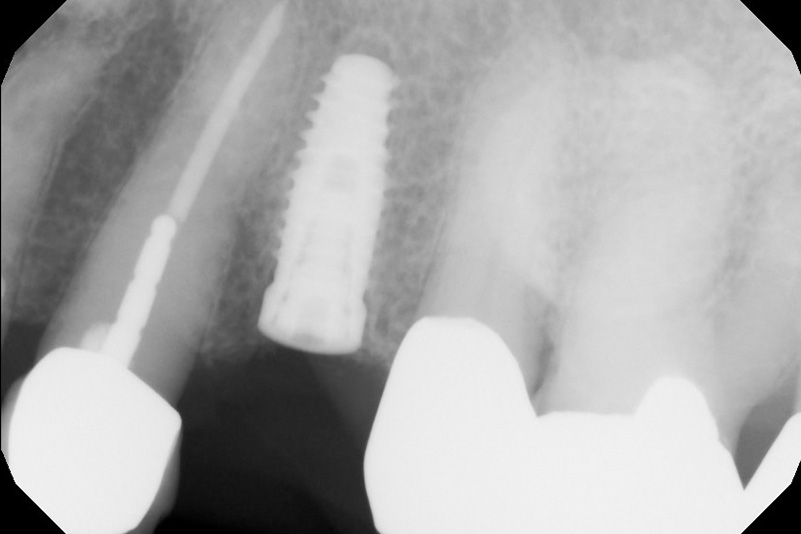

The journey from having a missing tooth to getting a dental implant is a several-step process. After ensuring you are a good candidate for a dental implant, we will schedule you for your initial surgical procedure. During the first surgery, a titanium post will be embedded into the bone and under the gum line where your natural tooth used to be. After this surgery, we will allow several months for the site to heal.

When the site is ready, Dr. Amato performs a second surgery to remove the gums that have naturally grown over the implant post to expose the tops of the implants. An abutment and natural-looking prosthetic tooth will be bonded to the implant. The goal is to give you a functional tooth replacement that blends right in with your smile!